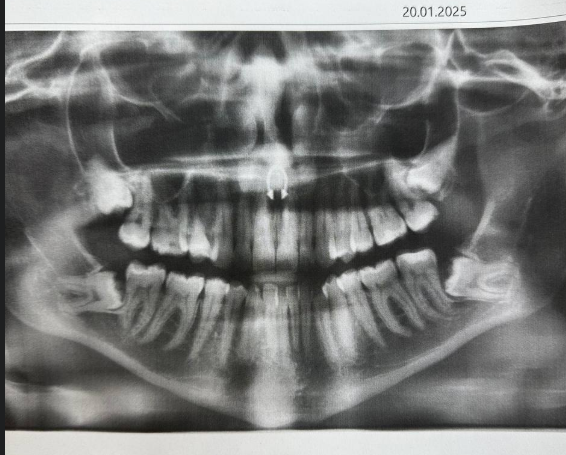

Мне выдали распечатку с панорамным снимком и флешку. Увидев снимок я немного была в шоке, и подумать не могла что так бывает — все зубы мудрости не прорезались и растут в корни других зубов.

Так, в середине лета я снова занялась зубами, и вместе со всеми своими сомнениями пошла к стоматологу-хирургу. Врач посмотрел на снимок, посочувствовал и сказал, что все 4 зуба мудрости надо удалять именно в ЧЛХ (челюстно-лицевая хирургия), выписал направление, дал номер по которому нужно записываться в больницу на консультацию.

Буквально за пару дней до даты госпитализации я решила зайти в еще одну стоматологию и сделать повторное КТ (а то первому уже полгода было), заодно сходила на консультацию. Там мне врач сказала всё, что я и так знала, но боялась принять — нужно удалять все 4 зуба, так как они все растут в корни семерок, значит в один момент начнут их портить, а корни не лечатся. Также мне сказали, что надо исправлять прикус. Я позадавала тупые вопросы про боль и восстановление (чего я больше всего боялась), меня уверили, что это достаточно стандартная операция и не стоит переживать, а чтобы боли не было мне будут делать обезболивающие уколы. В целом так и получилось.